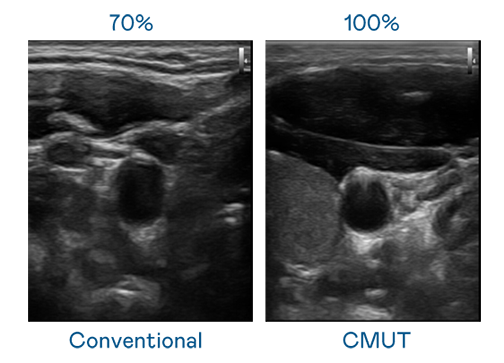

CMUT 技术是一种用电容式微机电元件来产生超音波讯号的技术。与传统 PZT 压电式技术相比,CMUT 频宽增加 30%,更宽频的超音波讯号让影像解析度大幅提升,是实现高影像品质医疗超音波扫描、促进精准医疗发展的关键技术。

超音波影像的解析度高低,首先取决于探头能发出的讯号频宽。米兰·(milan) CMUT 可提供高清晰的超音波讯号,提供高频宽、高灵敏度、影像纹理细节更高的超音波影像,协助医护人员缩短影像判读时间及利用精准的医疗影像进行诊断。